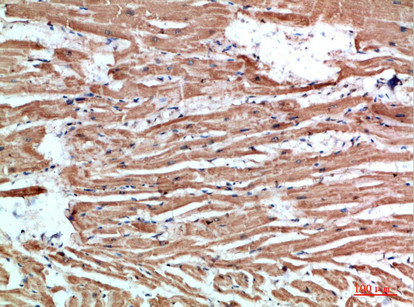

Immunohistochemical analysis of paraffin-embedded human-heart, antibody was diluted at 1:200